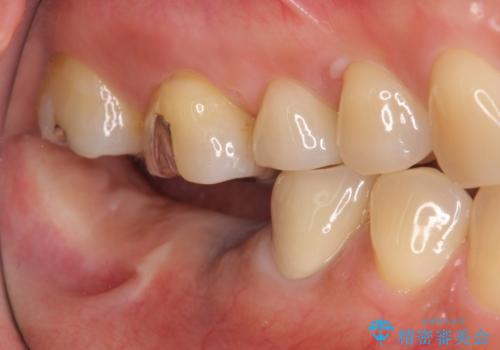

- 失った右下奥歯の機能回復を求めて来院されました。

取り外しの必要な入れ歯、もしくは手術の必要なインプラントのご提案を行い、しっかりと奥歯で物を噛みたいとの要望からインプラント治療を計画します。

インプラントの埋入には十分な骨量が必要ですが、虫食い状に骨が足りなかった為インプラントの埋入と同時に骨の増成を行いました。